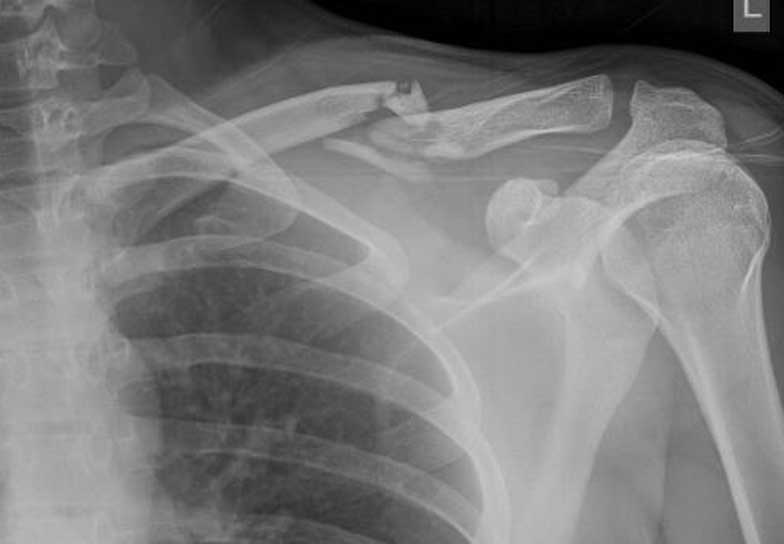

A sértett a bántalmazás következtében 8 napon túl gyógyuló felkarcsonttörést szenvedett.